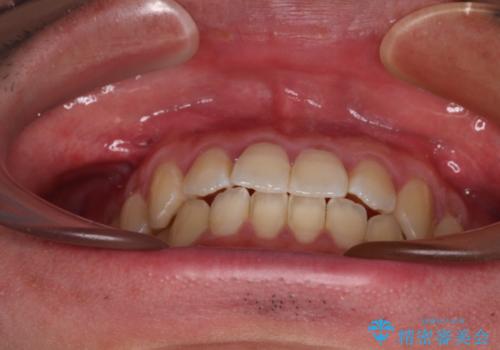

- 上下前歯のデコボコを気にして来院された患者様です。

叢生は軽微であり、費用を抑えて期間もあまりかけずに治療をしたいとのことで、インビザライン・ライトを用いて矯正治療を行うこととしました。